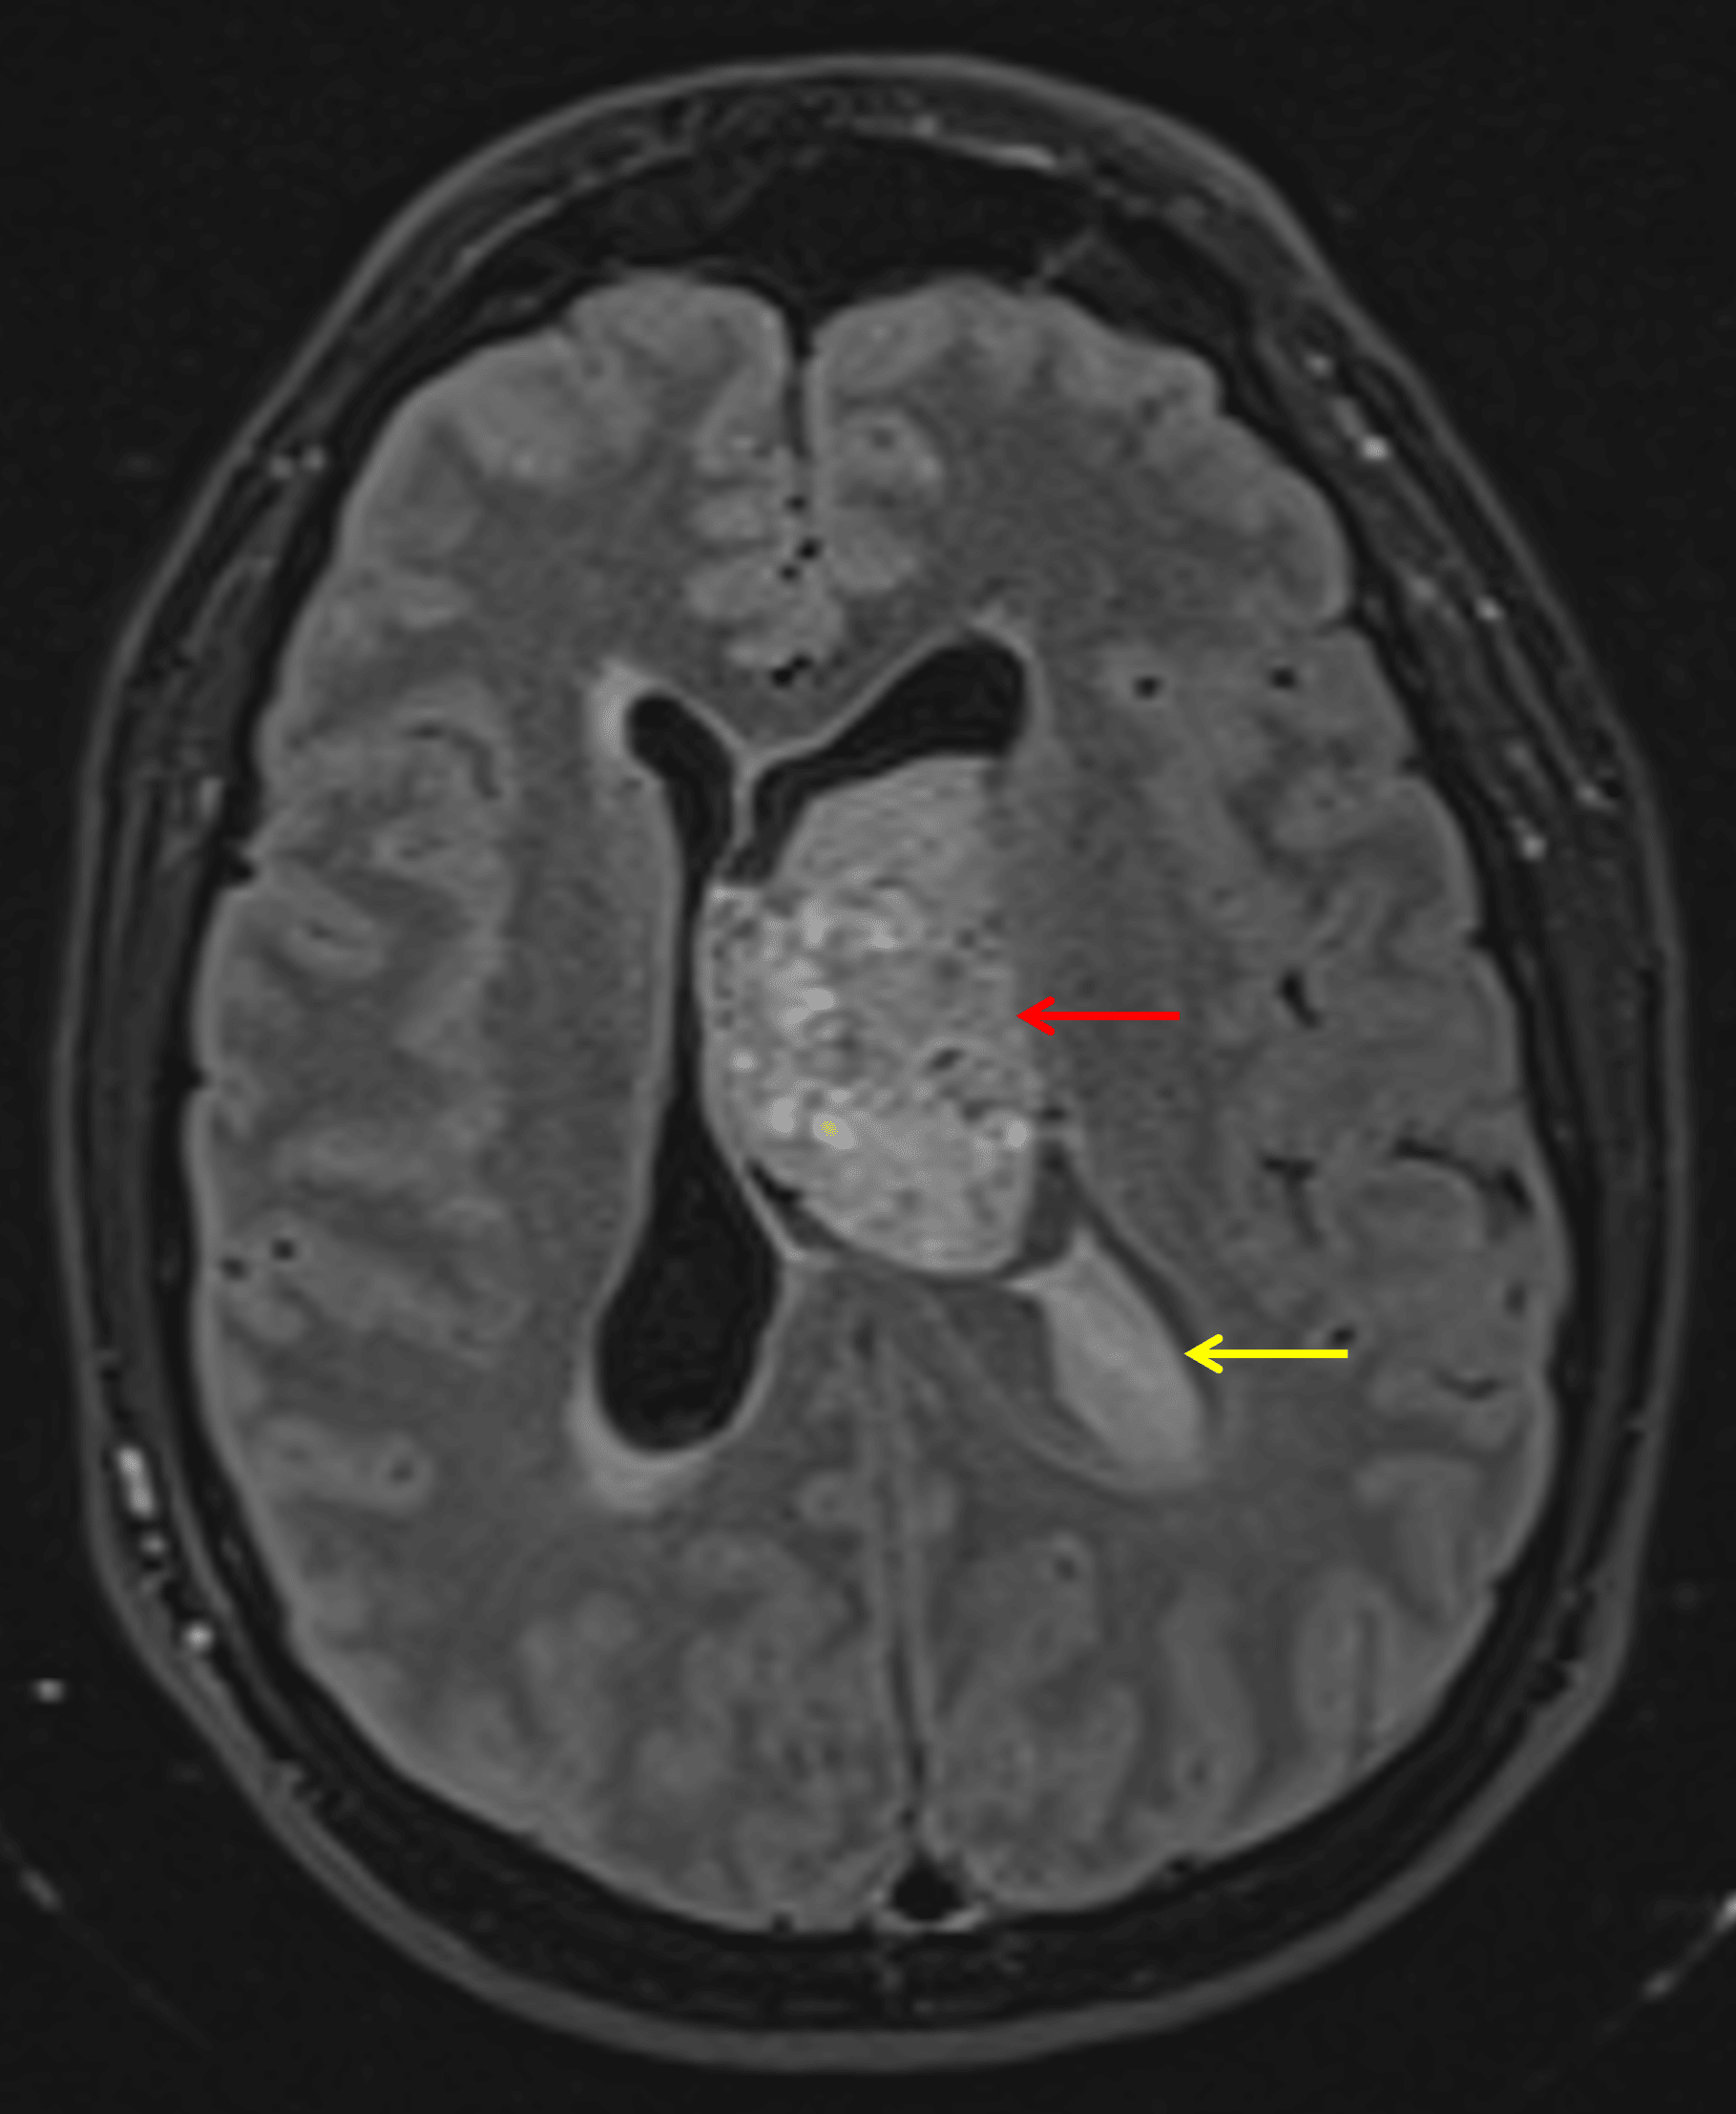

• Mildly FLAIR hyperintense intraventricular mass in the body of the left lateral ventricle measuring 4.3 x 3.7 cm in axial dimensions with heterogeneous corresponding enhancement and restricted diffusion

• The mass broadly contacts the septum pellucidum

• Associated mass effect with 1.5 cm left-to-right midline shift

• Crowding of the foramen of Monro with enlargement of the left greater than right lateral ventricles, consistent with obstructive hydrocephalus

• T1 isointense, FLAIR hyperintense material alongside the mass and layering in the left greater than right lateral ventricles and third ventricle, most likely representing hemorrhage (likely related to ventricular drain placement)

Mildly FLAIR hyperintense mass in the left lateral ventricle abutting the septum pellucidum (red arrow). Hyperintense material layering in the left lateral ventricle likely representing hemorrhage (yellow arrow).